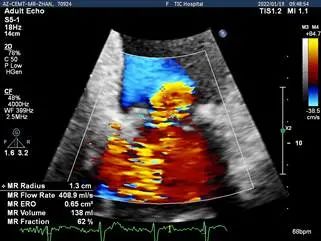

Bicom:MR(重度),反流束宽15mm,反流面积14cm²,PISA法定量EROA:0.65cm²,Rvol:138ml,RF:62%,r:13mm

二尖瓣反流频谱呈全收缩期

肺静脉血流频谱呈收缩期反向

3D MV View:P2区脱垂,宽16.3mm,P3区瓣叶膨隆,与前叶对合不良

3D-color MV view:大量反流,起源于2区